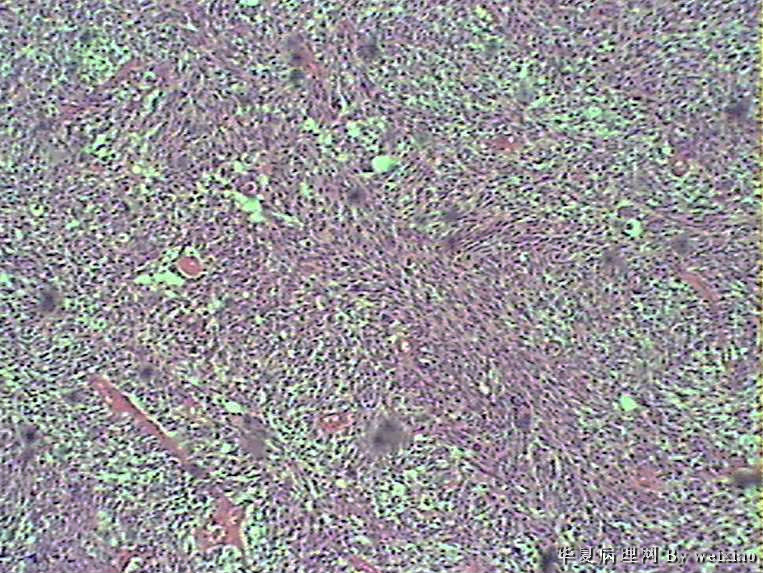

病史:男45岁,头痛2个月,手术所见:额叶占位性病变,与周围正常脑组  织的界限不清。

大体:灰白色碎组织一堆,质软,大小:2.5*1.8*1.3cm

×参考诊断

胶质母细胞瘤

坏死+细胞密度+异性+围绕血管现象。

考虑血管外皮瘤

脑膜瘤,查看核分裂和肿瘤侵犯程度。

不典型脑膜瘤

血管外皮瘤,SFT.

会诊胶质母细胞瘤

The tumor cells are kind of spindle, need to rule out gliosarcoma, you need to check MRI films, do immunostain for GFAP, and vimentin. The vascular proliferation (VP) supports GBM.

肿瘤细胞呈梭形,血管增生明显,有坏死,符合胶质母。